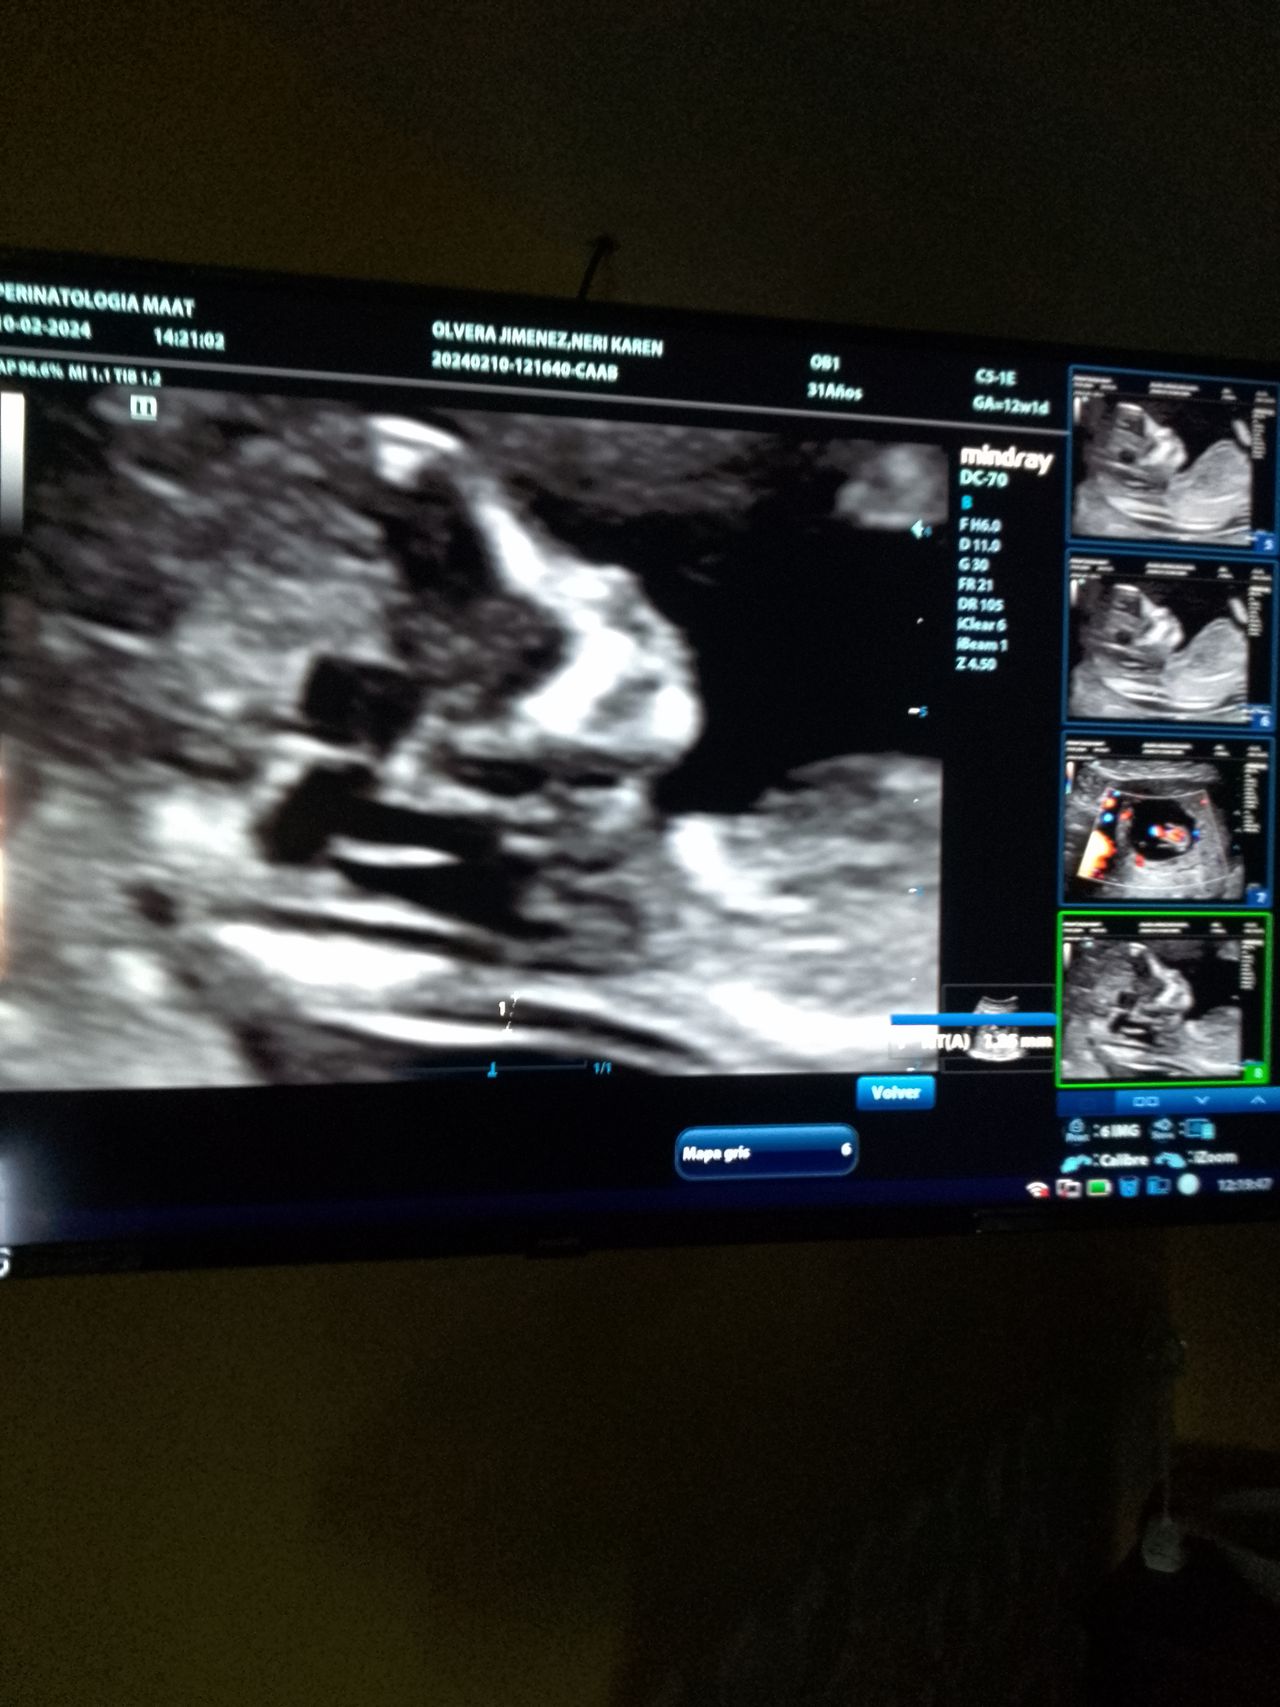

Fotos y videos

Galería